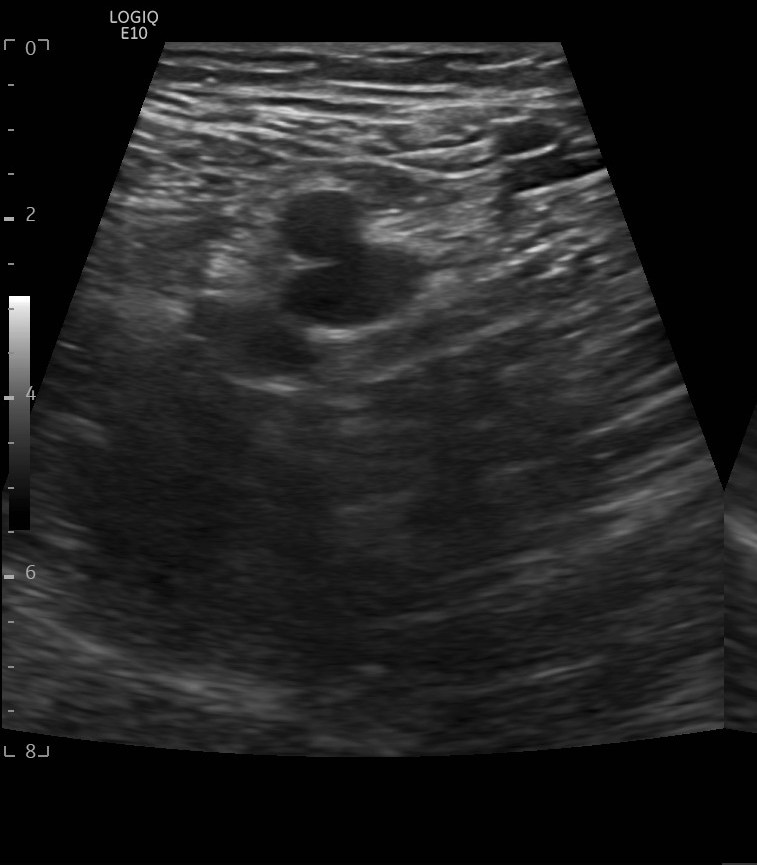

Hallazgos ecográficos

Hallazgos ecográficos: se realiza una ecografía del sistema venoso profundo en 2 puntos demostrando la completa compresibilidad del mismo, no presencia de material ecogénico y buenos flujos en el Doppler color, descartándose trombosis venosa profunda (TVP).

Se realiza una ecografía cutánea: se observan imágenes de “patrón en empedrado o adoquinado”, sugestivo de posible celulitis.